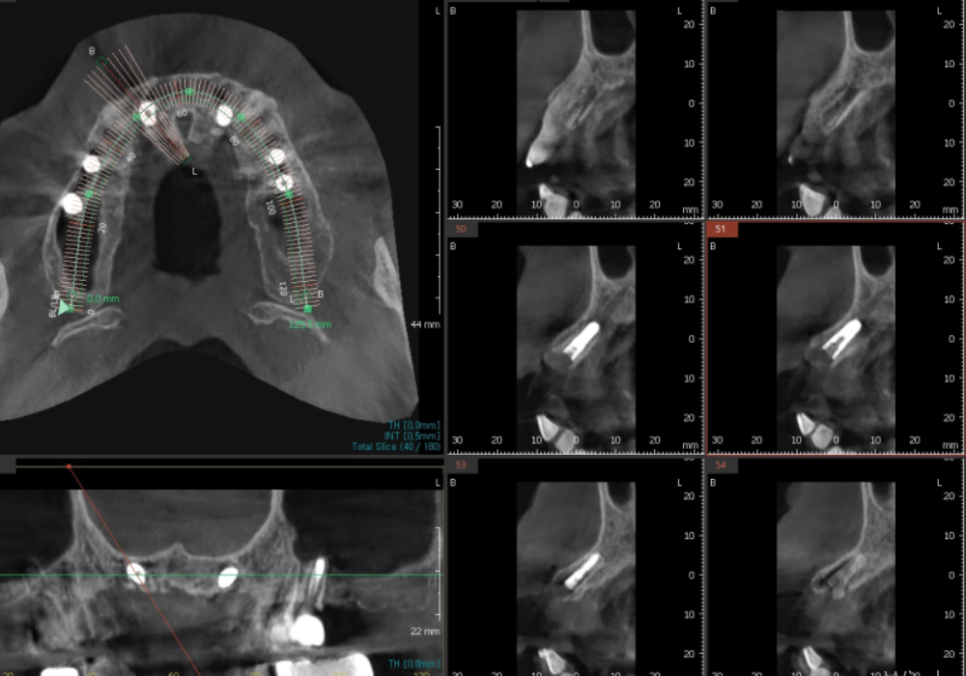

그래서 바로 치료부터 들어가기보다는,

3D CT로 안쪽 상태를

한 번 더 자세히 살펴봤습니다.

수술 전에는

3D CT를 통해 위치를 하나씩 확인하며

계획을 세웁니다.

여러 각도로 살펴본 결과,

가장 안정적으로 버틸 수 있겠다는

위치를 기준으로 계획을 잡았습니다.

250221